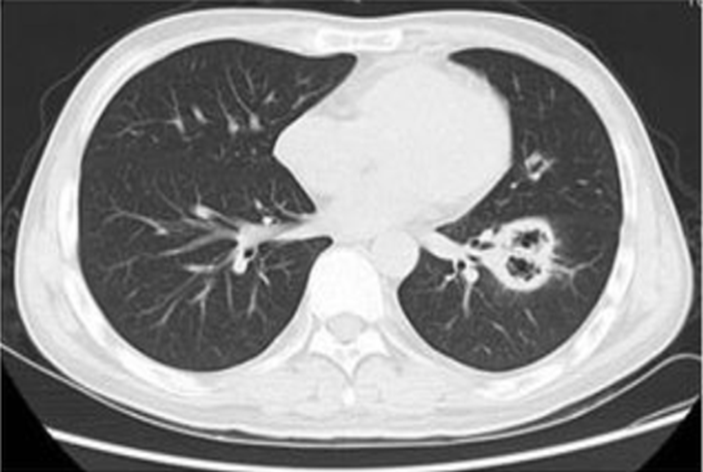

不同免疫抑制类型患者所特有的SCAP病原体,例如,粒缺患者首先考虑铜绿假单胞菌和曲霉感染的可能,艾滋病患者考虑肺孢子菌和结核分枝杆菌感染风险,T细胞耗竭(抗胸腺细胞球蛋白、阿伦单抗)患者考虑肺孢子菌、隐球菌以及单纯疱疹病毒感染,低丙种球蛋白血症患者考虑呼吸道合胞病毒感染,使用神经磷酸酶抑制剂(环孢素、他克莫司)患者要考虑诺卡菌或曲霉感染,使用雷帕霉素抑制剂的患者需考虑隐球菌或曲霉感染风险,使用糖皮质激素的患者首先考虑铜绿假单胞菌及肺孢子菌感染风险。

(7)免疫抑制患者的经验性抗水痘-带状疱疹病毒指征,①临床特征:双肺多发结节浸润伴水疱性皮疹。②治疗推荐:阿昔洛韦10~15 mg/kg q8h。